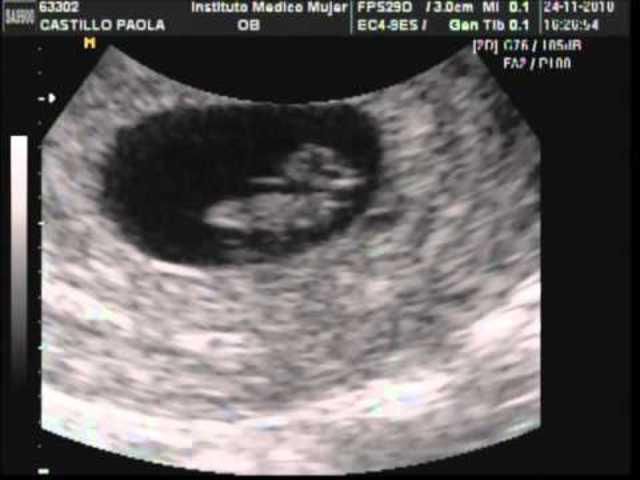

Implantación:

Corresponde al momento en que el blastocito toma contacto con el endometrio y comienza a invadirlo